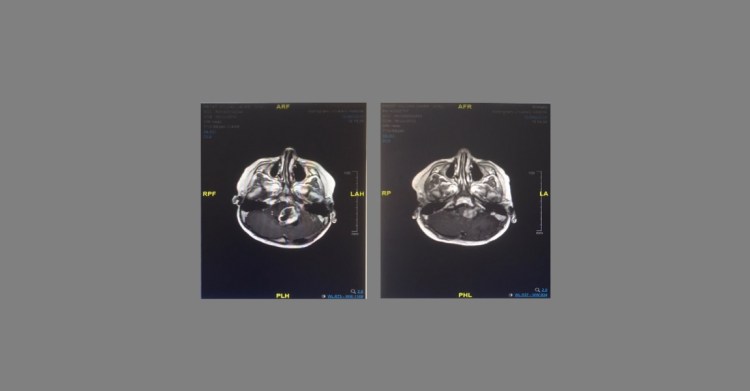

I’m not sure why but I’ve never shared these images before – here they are… MRI’s taken six months apart – the first being taken just before we started the Diet and CBD and the second showing the two third reduction.